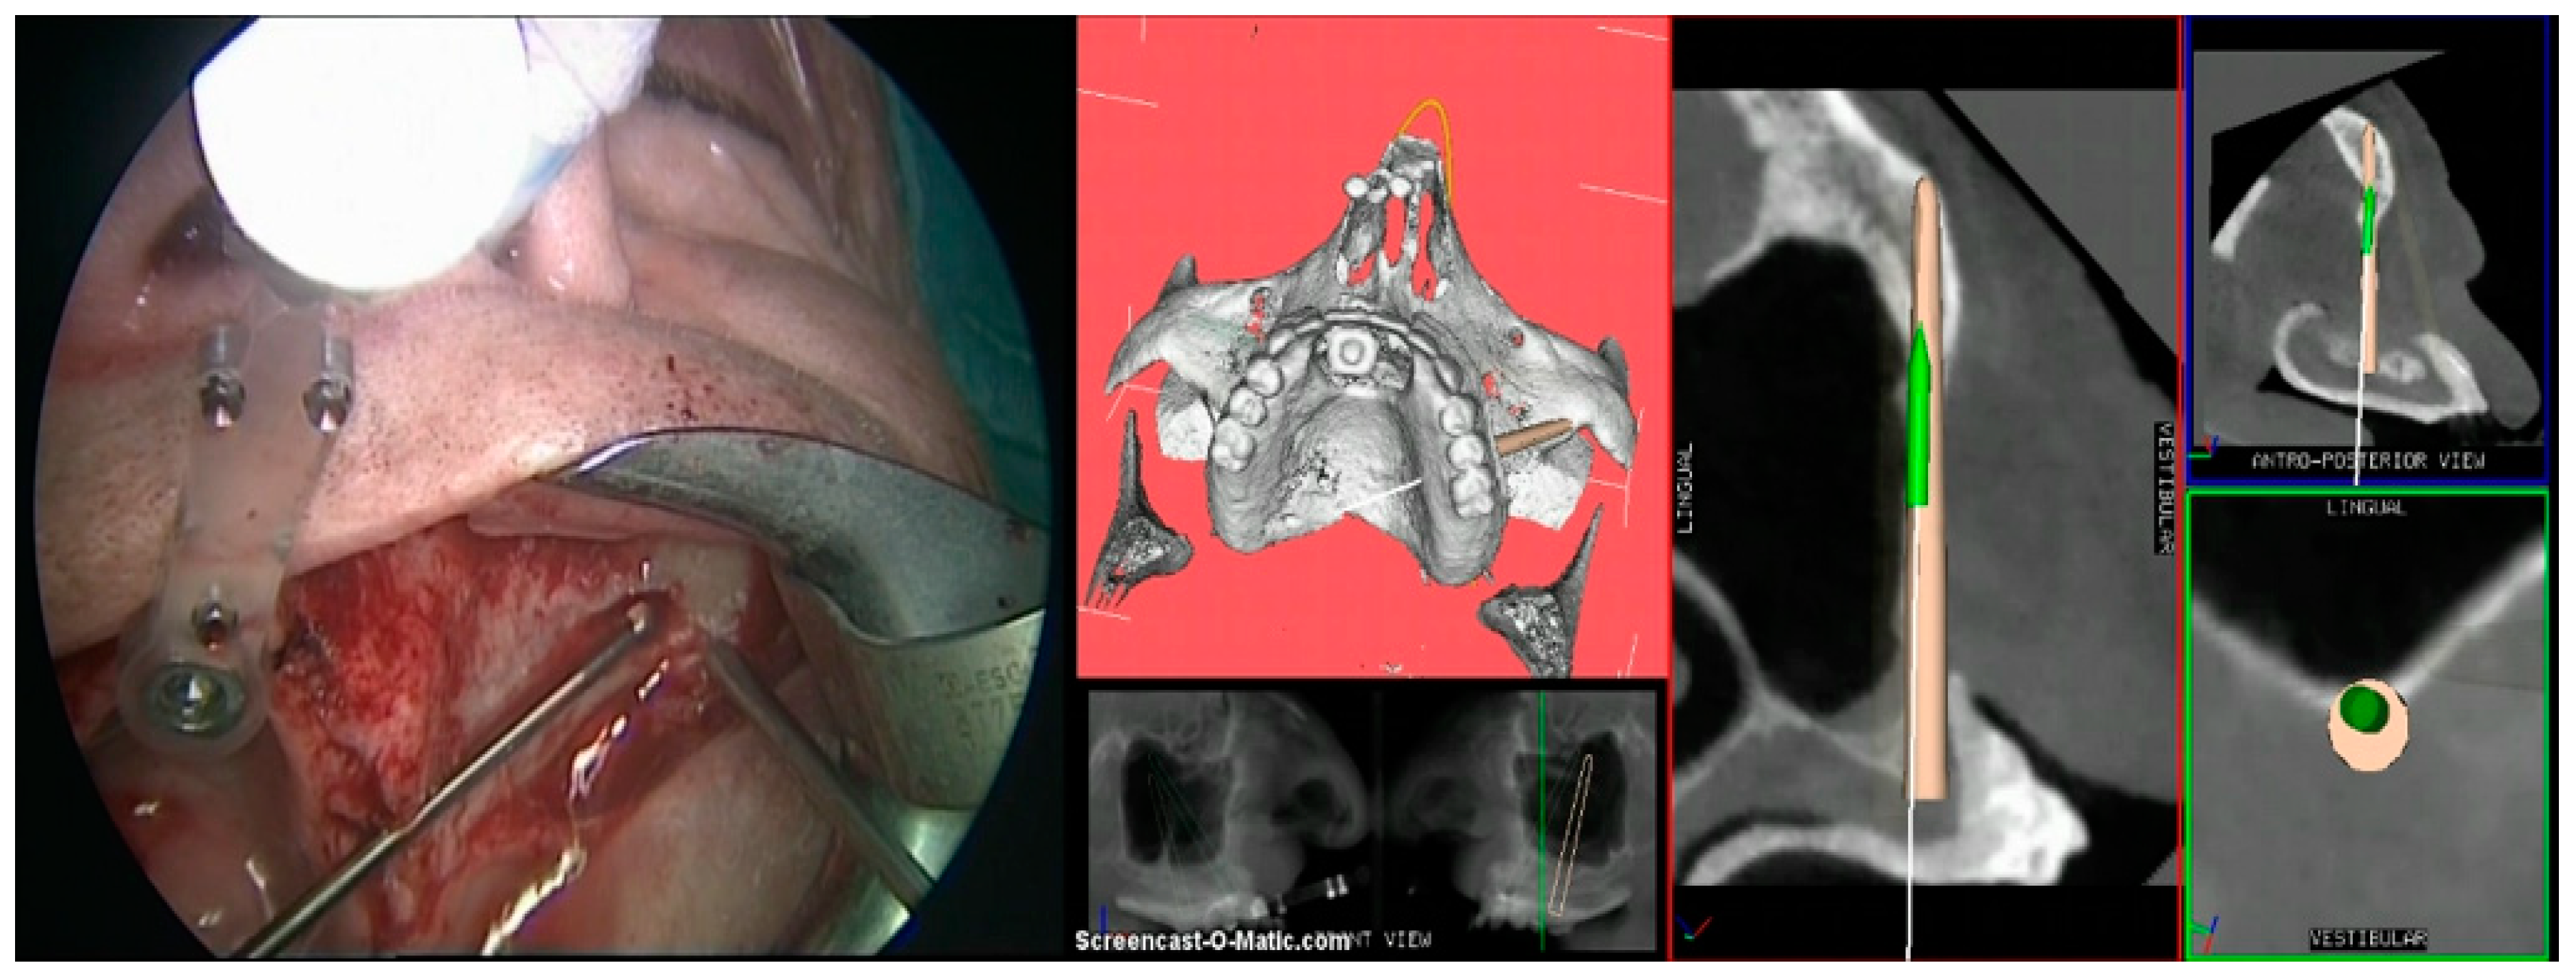

- Step 3. Image-to-patient registration via registration templates, external registration frames, or bone markers.

- Step 4. Surgery: navigation of the drill along the predefined surgical plan.